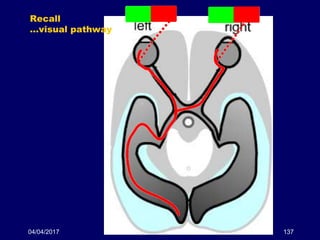

04/04/2017 137

Recall

…visual pathway

04/04/2017 138